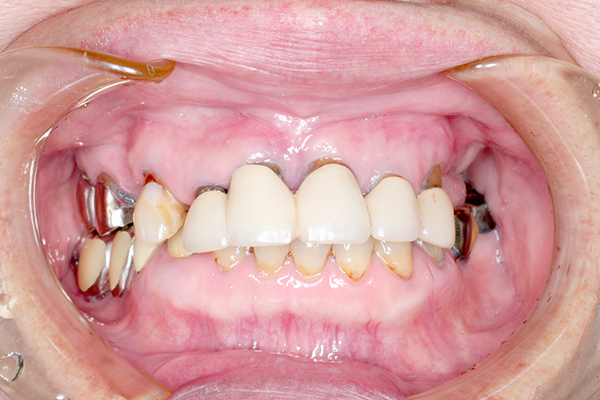

インプラントの症例

50歳女性

70歳女性